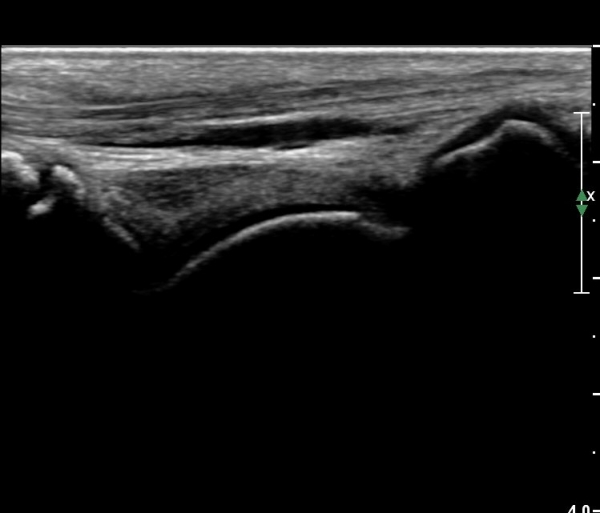

°ÇÃø °Å°ñºñ°ñÀδë Á¾´Ü¸é°Ë»ç¿¡¼­ Á¤»óÀûÀÎ ¼Ò°ßÀ» º¸À̰í(»çÁø 6),

¹ß¸ñ°üÀý ¾ÕÂÊ Á¾´Ü¸é°Ë»ç¿¡¼­ °üÀý³» ¼ö¾×Àú·ù°¡ »ç¶óÁö°í(»çÁø 1),